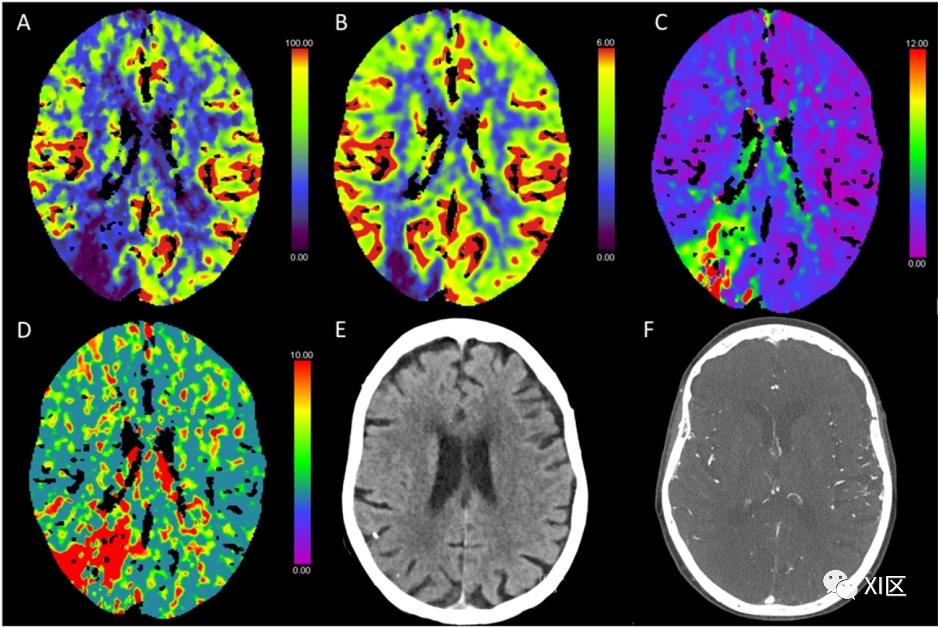

图1、图2、图3和图4给出了急性幕上卒中的例子。图5是一个恶性右侧MCA梗死的随访检查。

图3 脑部CTP生成的彩色编码图:(A)脑血流量(CBF)[mL/100 g/min],(B)脑血容量(CBV)[mL/100 g],(C)Tmax [s],以及(D)平均通过时间(MTT)[s]。(E)NECT和(F)动脉CT血管成像(CTA)最大密度投影(MIP)图像。该患者在经导管主动脉瓣植入术(TAVI)后出现异物感并昏迷。在NECT图像上,没有发现脑实质的缺血性改变。CTP发现CBF强烈降低,CBV正常,导致Tmax和MTT强烈延长,这与急性缺血事件相一致,表明有一个大的半影,没有环形的缺血核心。CTA显示基底动脉顶端有血栓性闭塞。